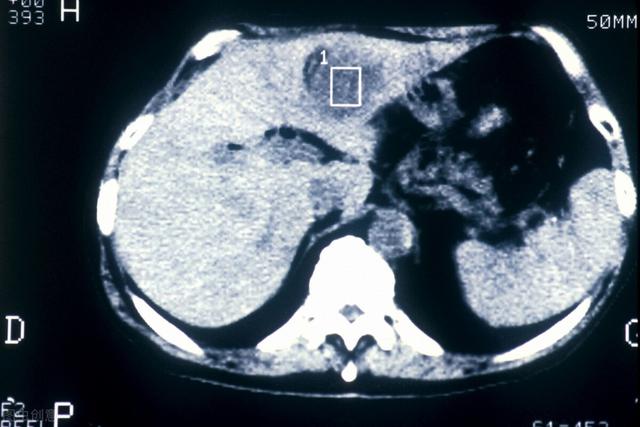

- 肝臓の超音波検査で肝臓に腫瘍が見つからない場合、または腫瘍の性質が判断できない場合、αフェト蛋白の上昇は肝細胞癌の可能性を強く疑わせる。さらに肝臓のCTを行うこともある。強化CTは肝臓腫瘍の特定に比較的優れているので、すぐに肝臓の強化CTをお勧めします。